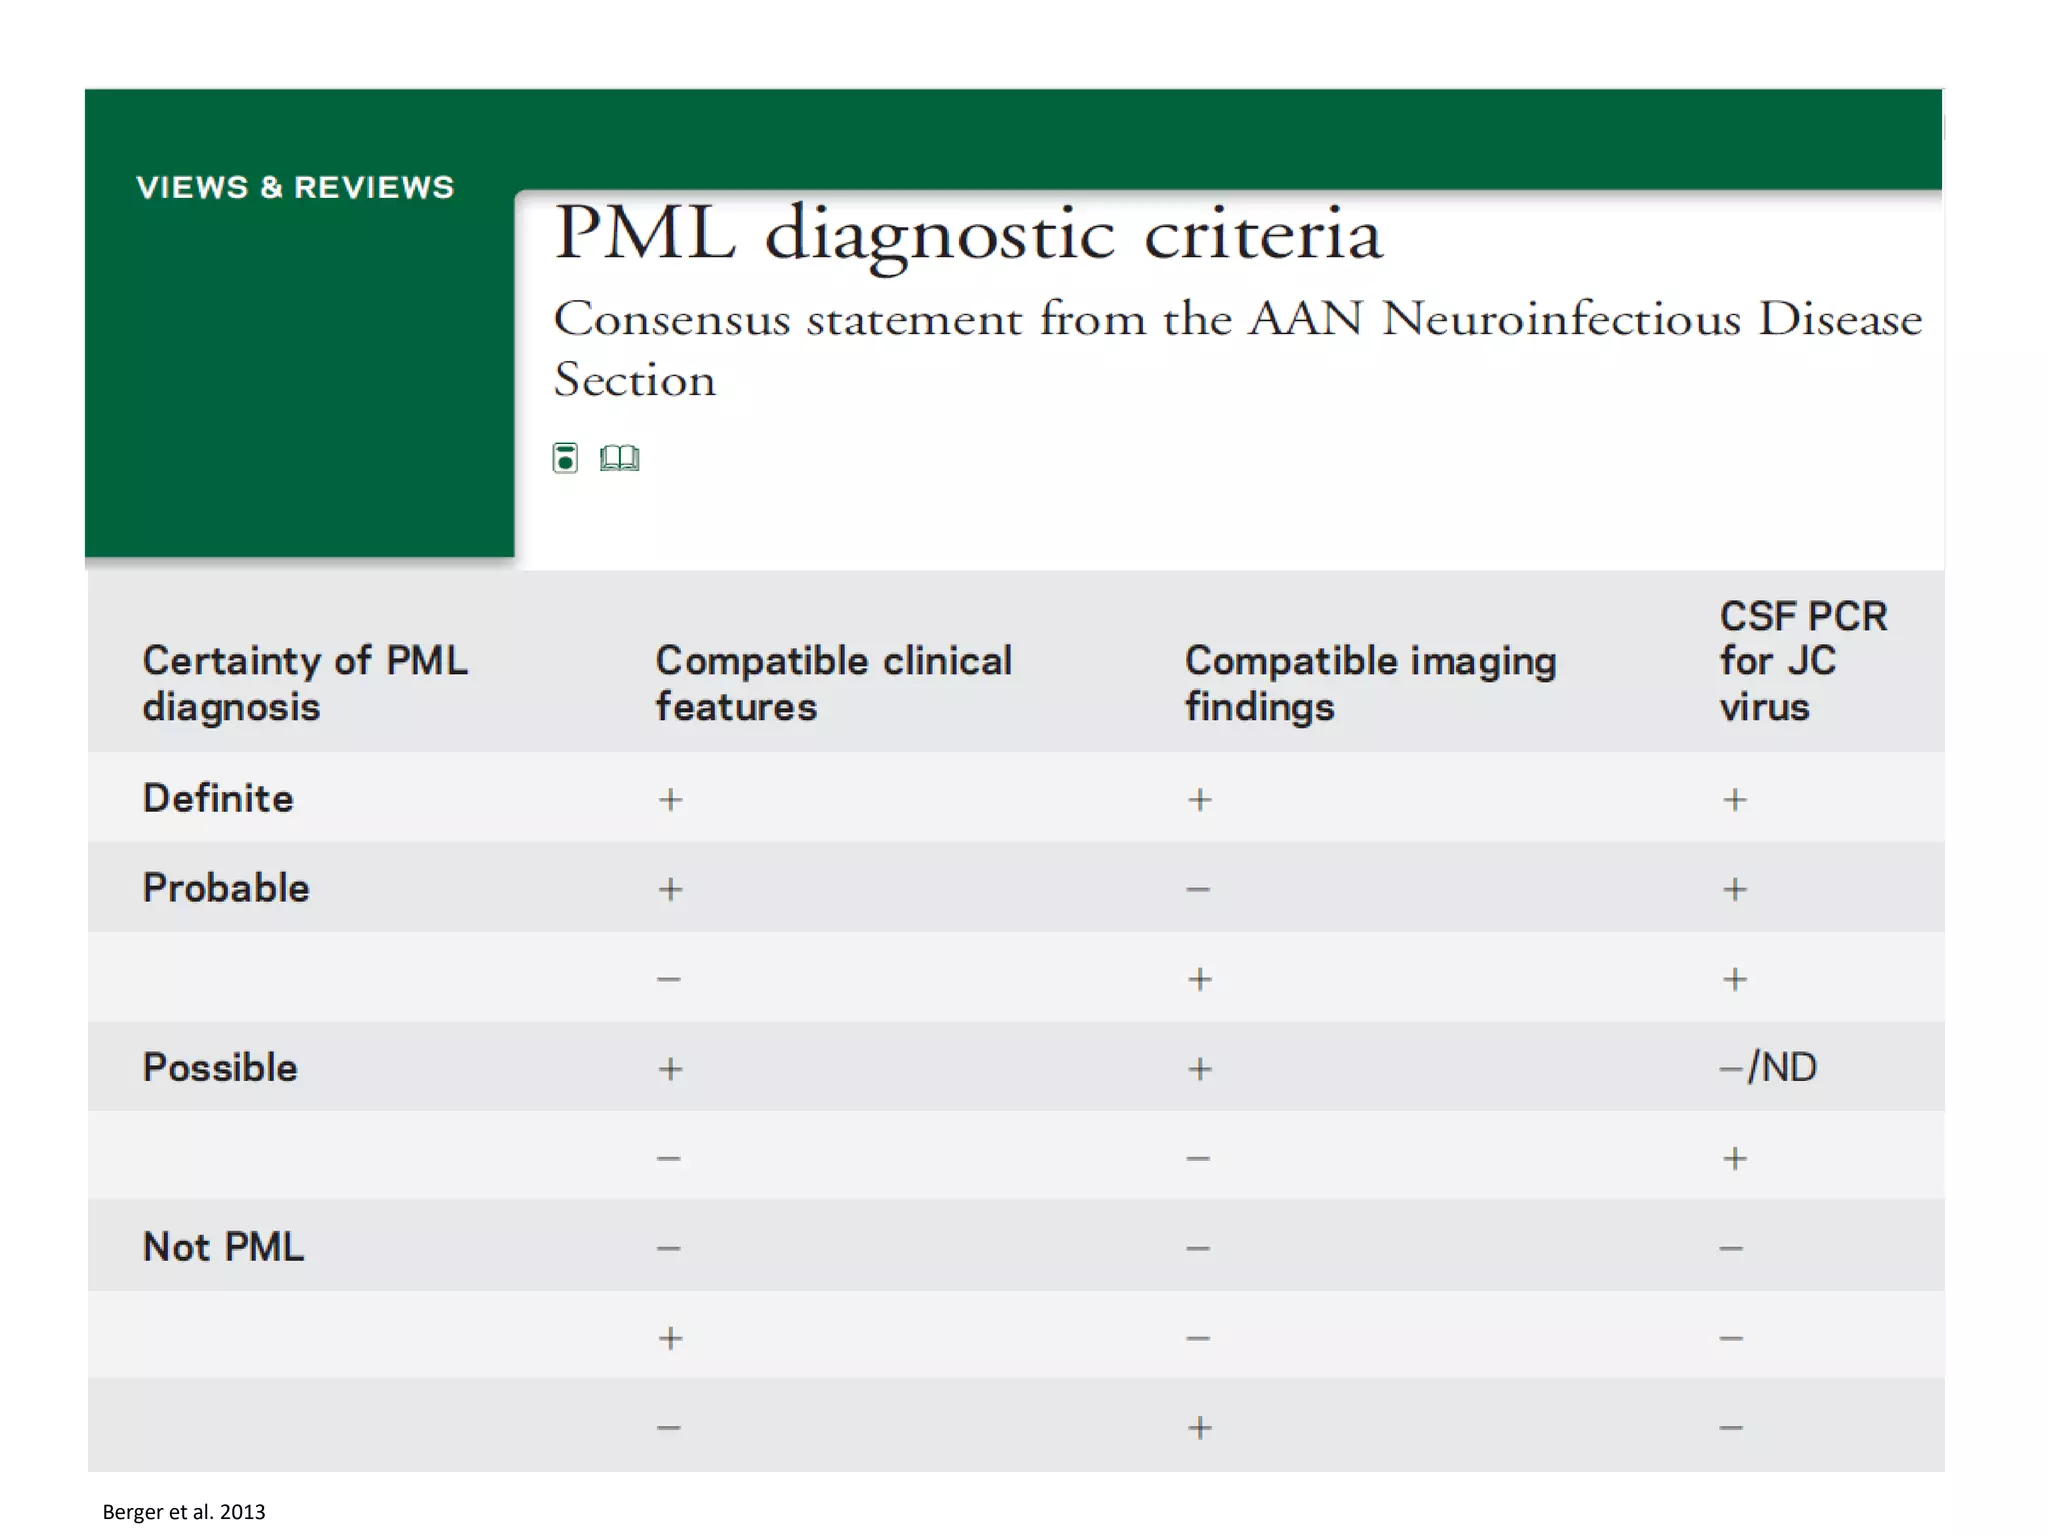

This document discusses progressive multifocal leukoencephalopathy (PML), an opportunistic infection caused by the John Cunningham virus (JCV) that leads to demyelination in the central nervous system. It highlights the epidemiology, clinical manifestations, diagnostic methods, and risk factors associated with PML, particularly in immunocompromised patients and those undergoing immunomodulatory therapies. It also presents data on the incidence of PML in patients treated with natalizumab and other therapies, addressing the relationships between these treatments and the development of PML.